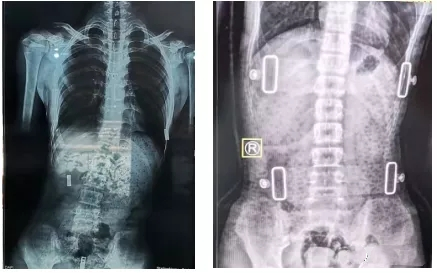

有時(shí)戴了支具后脊柱會(huì)反方向傾斜。其實(shí),這是因?yàn)橐话阒Ь咧委煏?huì)采取一種“過(guò)度矯正”的方式,以保證脫下支具后身體的反彈更接近于中心線,而不是向原側(cè)彎方向加重。